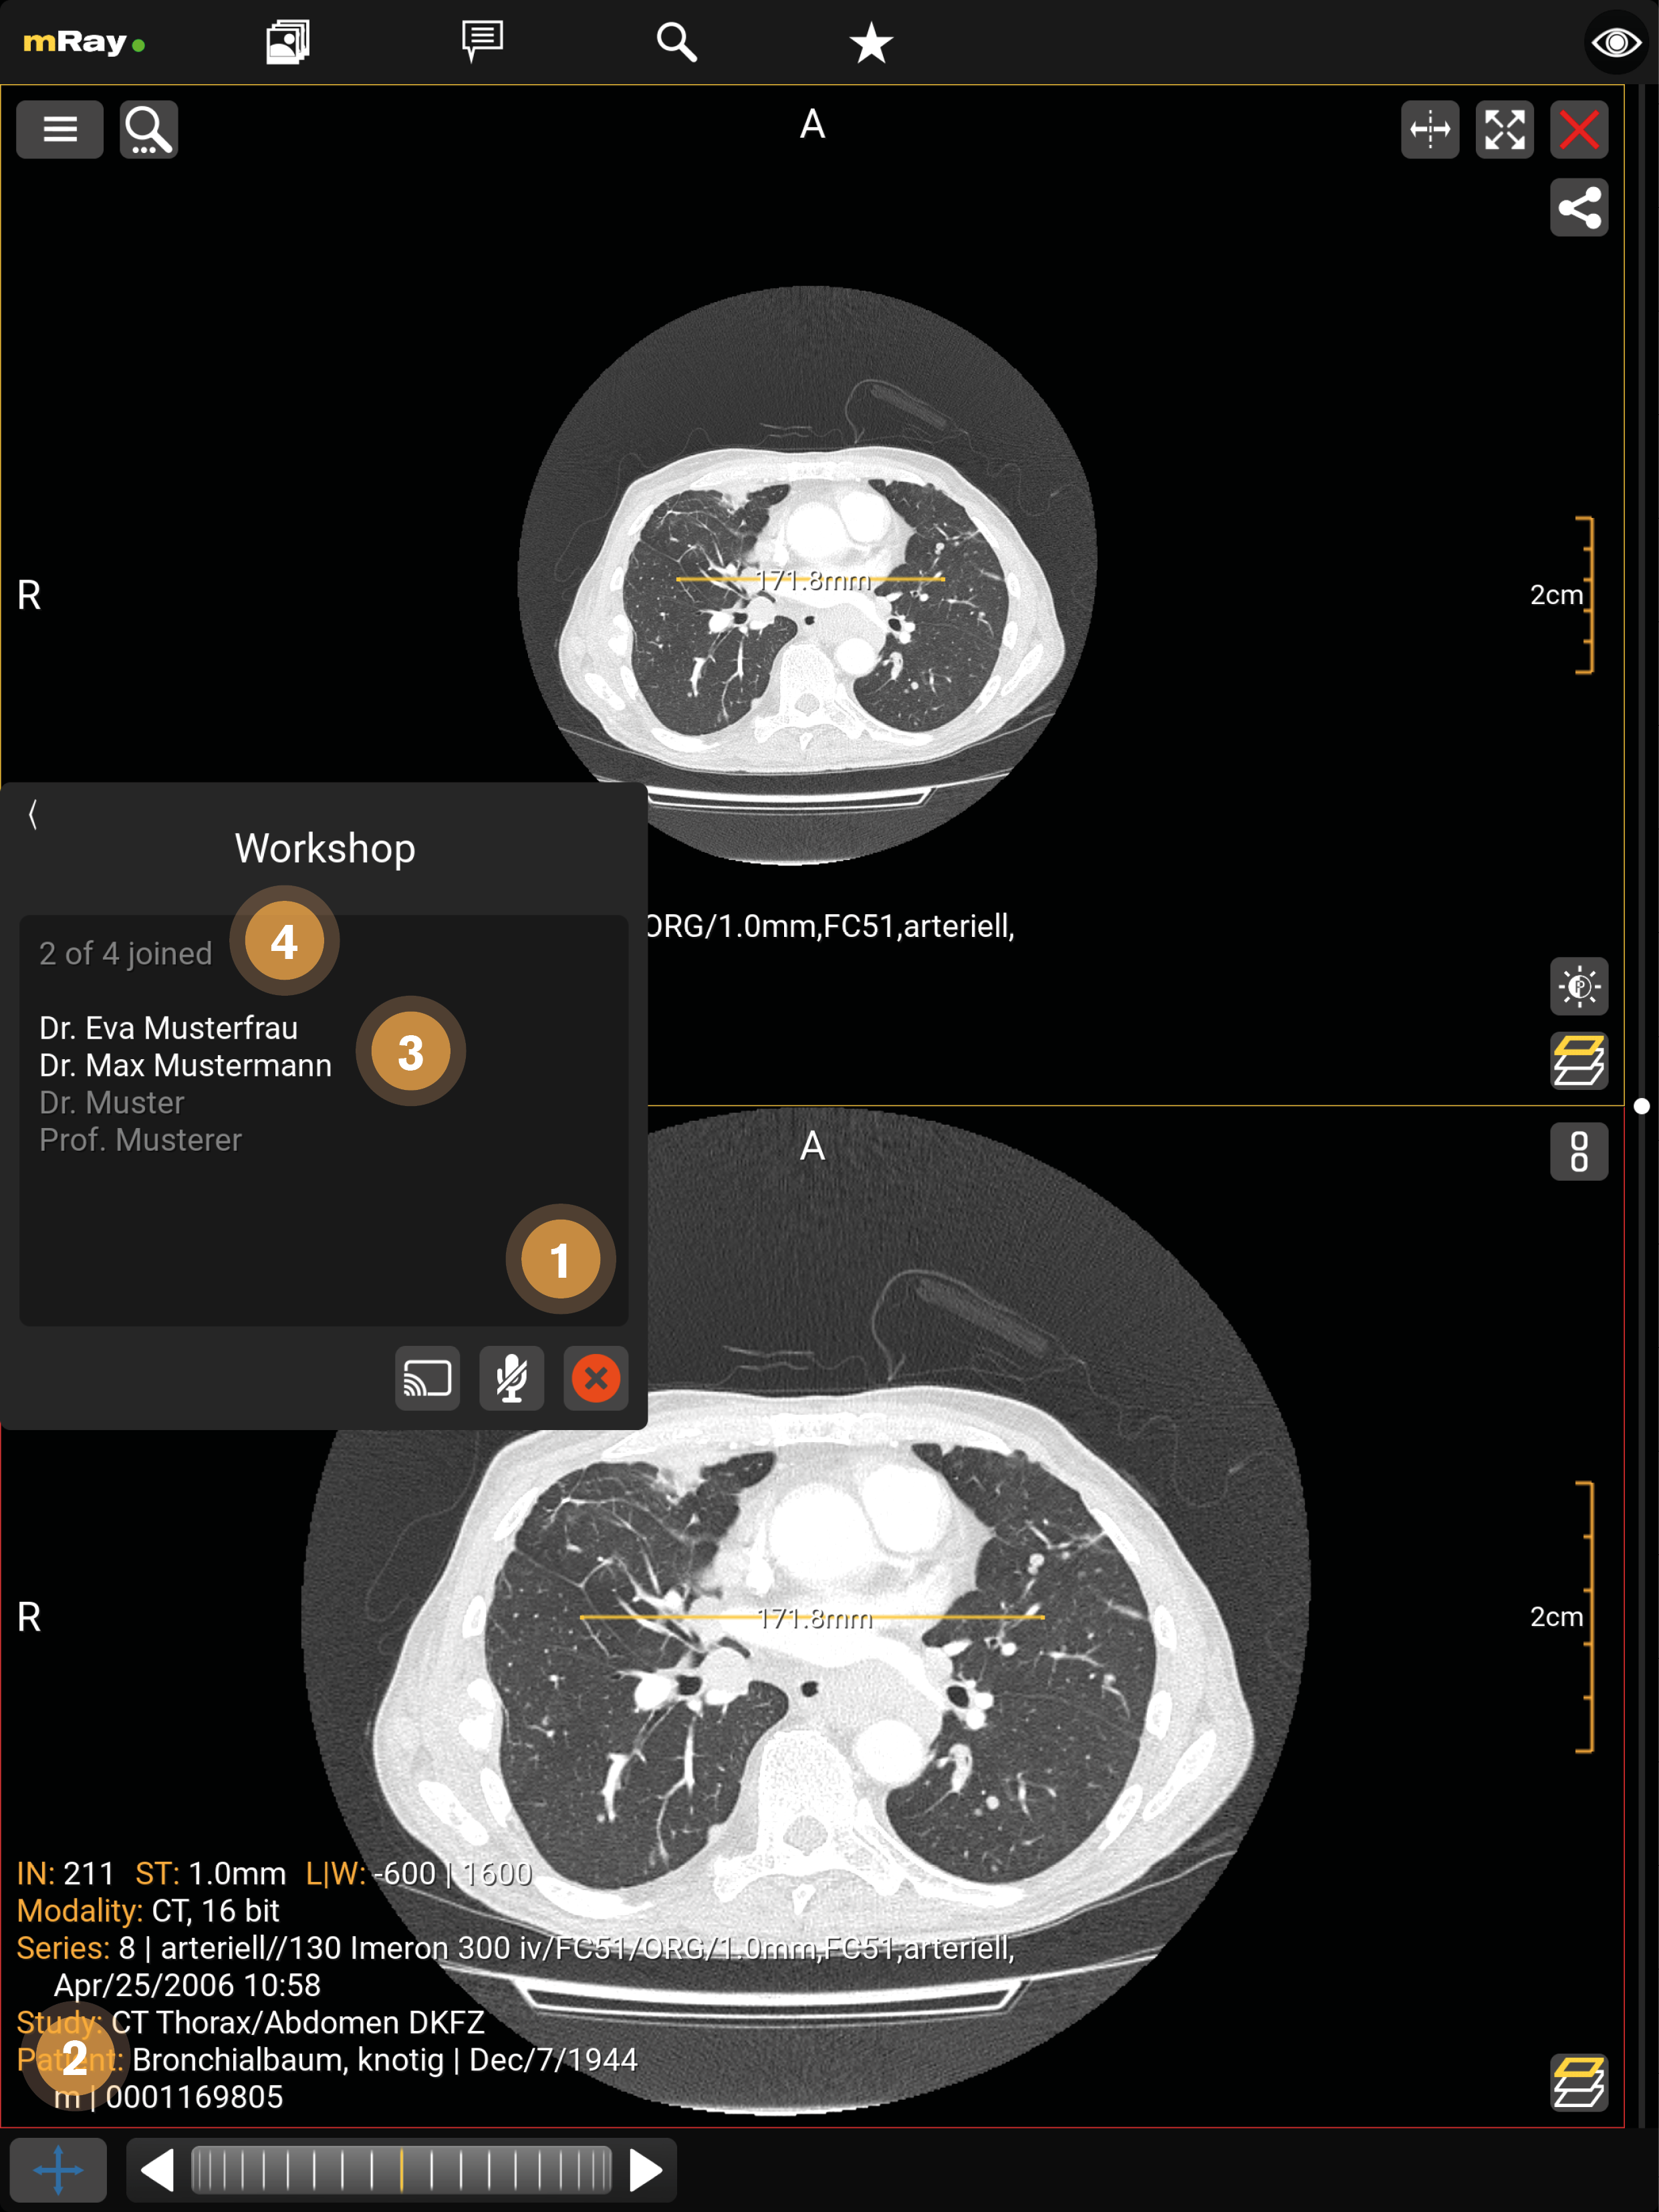

14. Screensharing

Screensharing allows you to share your screen with others. After pressing the button (see Chat) the screensharing will start and the image you have already opened will open (see Chat) or you will be redirected to the inbox if no image has been opened yet. The screensharing can be started with one or more persons (see Screensharing in groups), in the form of a group.

In a chat, the administrator is the one who starts the screensharing. In a group the administrator is defined previously (see Screensharing in groups).

The upper figure visualizes the following functions:

-

The one who started screensharing is underlined in white, the active participants are displayed in white and the inactive participants of the group are displayed in gray.

-

With the 'Microphone' button, a participant can activate and terminate the voice function (crossed out). The speaking participant is displayed in yellow.

-

The X button ends the screensharing for all participants.

-

Only the administrator can apply tools during the screensharing.

-

Here you can minimize the window.

The upper figure visualizes the following functions:

-

By clicking the 'green checkmark' button, the participant can join the screen sharing.

-

The administrator is underlined in white, the active participants are displayed in white and the inactive participants of the group are displayed in gray.

14.1. Screensharing in groups

In a group, screen sharing can only be started by a previously determined administrator. For the other participants of the group, the screen sharing starts automatically. In a group only the group administrator can use the voice function.

The upper figure visualizes the following functions:

-

The X button ends the screensharing for all participants.

-

Only the administrator can apply tools during the screensharing.

-

The one who started screensharing is underlined in white, the active participants are displayed in white and the inactive participants of the group are displayed in gray.

-

The number of active participants and all group members.